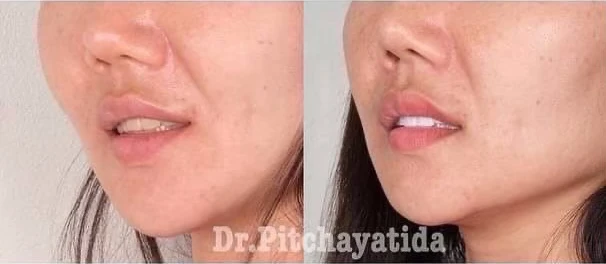

“อย่างเรื่อง การแก้ไขความผิดปกติของฟัน เช่น ฟันตกกระ แก้ไขรูปร่างฟัน พวกนี้ หมอฟันต้องดูด้วยว่า ฟันแบบไหนจะเหมาะกับรูปหน้าของแต่ละคน ผู้หญิงและผู้ชายก็มีฟันรูปร่างและขนาดต่างกัน ซึ่งหมอฟัน จะต้องดูและออกแบบว่า ฟันแบบไหน ถึงจะเหมาะสมและสวยงาม สำหรับ ผู้ที่เข้ามารับการรักษา”